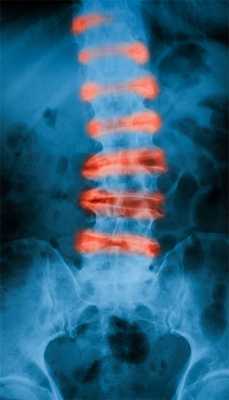

Болезнь Бехтерева или анкилозирующий спондилоартрит — хроническое системное заболевание суставов, которое поражает преимущественно крестцово-подвздошные сочленения, суставы позвоночника и паравертебральные мягкие ткани. Врачи пока не установили достоверные причины развития недуга. Предположительно, болезнь Бехтерева развивается из-за патологической реакции иммунной системы на ткани суставов и связок. Спровоцировать такую реакцию может переохлаждение, хронические инфекции, перенесенные травмы позвоночника, гормональные сбои.

Изначально недуг проявляется неспецифическими симптомами: слабостью, повышенной сонливостью, неприятными ощущениями в мышцах и суставах. По мере прогрессирования проблемы к этим признакам присоединяется скованность в пояснице, которая усиливается по утрам и стихает при активном движении. В дальнейшем боль поднимается вверх по позвоночнику, охватывает всю спину, физиологические изгибы спины сглаживаются и развивается кифоз. На поздних стадиях заболевание приводит к анкилозу, то есть сращиванию поверхностей сустава и потере подвижности.

Болезнь Бехтерева поражает позвоночник

Что происходит тем временем в организме? Воспаление появляется вне сустава в местах, где связки и сухожилия крепятся к кости. В основном распространяется на небольшие суставы, которые размещены меж позвонками. Главная особенность болезни Бехтерева - постепенное ограничение подвижности суставов, сращивание костей друг с другом (т.е. образование так называемых «анкилозов»), медленное превращение позвоночника в 1 цельную кость. Кроме того, окостеневают даже связки. Отсюда - потеря гибкости, возможности нормально передвигаться вплоть до полной неподвижности.